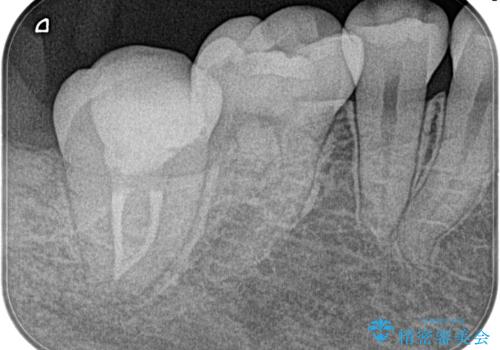

- 3日前からズキズキ痛み、冷たいものや熱いもので持続痛もあるとのこと。

不可逆性歯髄炎の診断で抜髄処置を行なっています。

- 精密根管治療(イニシャルケース,大臼歯):122,000円、ファイバーコア:22,000円費用は治療当時の料金となります